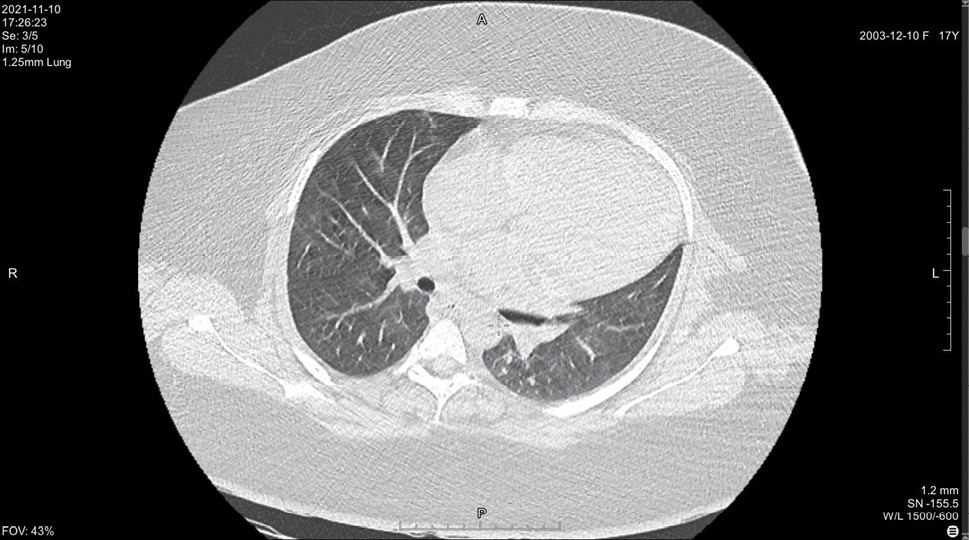

На 14 день болезни (10.11, 7 день госпитализации) была выполнена спиральная компьютерная томография грудной клетки, где выявлены признаки двусторонней интерстициальной полисегментарной пневмонии (рис. 1–8). Форма грудной клетки описана как обычная. Легочные поля расправлены. На томограммах бронхиальное дерево визуализировано до субсегментов: сами бронхи не деформированы, их просвет в пределах нормы, устья свободны, проходимость сохранена на всем протяжении. Во всех сегментах с обоих сторон определялись полиморфные, сливные участки уплотнения легочной ткани по типу матового стекла с участками консолидации. На этом фоне были видны просветы бронхов. Определялись фиброзные тяжи в проекции апикальной плевры обоих легких. Контуры диафрагмы четкие, синусы свободные, свободная жидкость в плевральной полости отсутствовала. Трахея обычной формы и размеров, карина острая. Сосудистые структуры верхнего средостения с четкими контурами и нормального диаметра, стенки сосудов без кальцинатов. Медиастинальные лимфоузлы и лимфоузлы корней обоих легких (без контрастного усиления) визуализированы единично, не увеличены. Сердце расположено обычно, размеры в пределах нормы. Выявлены умеренные дегенеративно-дистрофические изменения грудного отдела позвоночника. Мягкие ткани грудной клетки без особенностей. По заключению врача-рентгенолога, объем пораженной легочной паренхимы достигал 95%. Наиболее вероятно, что патологический процесс у пациентки имел вирусную природу.

Рисунок 1. Томограмма легких на уровне ThIII

Рисунок 2. Томограмма легких на уровне ThIV

Рисунок 3. Томограмма легких на уровне ThV

Рисунок 4. Томограмма легких на уровне ThVI